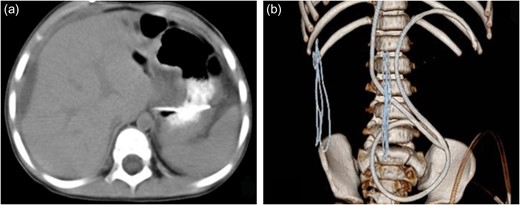

A female child, at the age of 2 years, was admitted to our hospital because she was not able to walk alone. This child patient had undergone ventriculo–peritoneal (VP) shunt procedure for hydrocephalus confirmed by magnetic resonance imaging (MRI). On the 50th day after the surgery, she mainly complained of intermittent fever and mild abdominal pain for 12 days. Physical examination showed no obvious abnormality. Blood routine examination showed white blood cell count was 8.31 × 109/l, with neutrophils 60.7%, lymphocytes 30.8%. C-reactive protein was 81 mg/l. Abdominal ultrasonography indicated ascites. Abdominal enhanced computed tomography (CT) scan showed that water-like hypointense mass in sub-capsular of liver, which was homogeneous and well-defined, the max cross-sectional area was ~6.04 × 3.85 cm, multiple catheter images were seen in abdominal cavity, also showed that there was no enhanced images in the mass (Fig. 1). Accordingly, it was necessary to perform exploratory operation. Operation found that a little of clear fluid was accumulated in abdominal cavity and the distal end of catheter was located at the sub-capsular of diaphragmatic surface of right liver. The distal end was pulled out slowly and sub-capsular effusion overflowed. The VP shunt catheter was neither disconnected nor fractured, and was replaced subsequently in abdominal cavity. Postoperative CT scan showed that a small part of effusion remained in the liver contour and the distal catheter in the left abdominal cavity (Fig. 2). The child was discharged uneventfully in 1 week postoperative.

The CT scan after operation. (a) Axial CT revealed a small part of effusion remained in the liver contour. (b) Three-dimensional image of catheter showed the distal catheter in the left abdominal cavity.